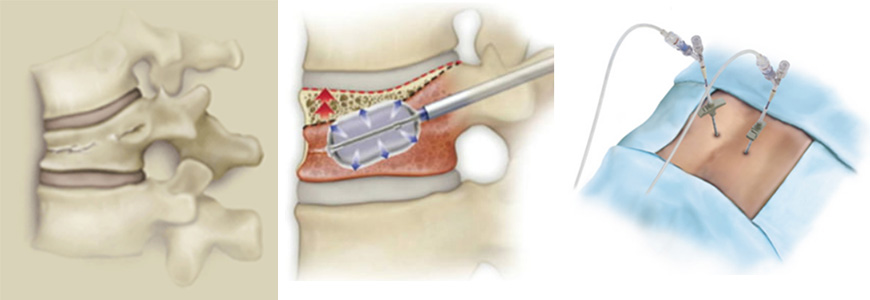

【椎体骨折の治療について】

圧迫骨折の急性期―亜急性期で傷みが引かず、除痛目的で行う手術です。

様々な手術がありますが、骨折椎体にセメントを注入する治療が低侵襲で手術時間も少なく普及しています。